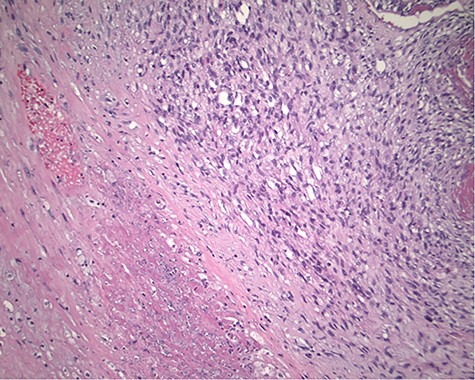

The pathology revealed a 282-g nodular tumor measuring 10.7 × 8.5 × 7 cm that was grossly tan, fibrotic and firm with focal yellow discoloration and soft flesh areas (Fig. 6). Microscopic analysis revealed high-grade spindle cell sarcoma arranged in intersecting fascicles with extensive areas of necrosis (Fig. 7). The lesional cells had fibrillary eosinophilic cytoplasm and evoid nuclei with nuclear pleomorphism (Fig. 8). Areas of rhabdomyoblastic and chondroid differentiation were also noted (Figs 9 and 10). Immunostaining was positive for desmin, focally for CD 34 and Bcl2, while Cam 5.2, CD117, S-100, SMA and HME45 immunostains show patchy staining for myogenin. Expression of H3K27me3 was completely lost in the tumor cells. MyoD1, SOX10, MDM2 and CDK4 were negative. It was identified as a high-grade MPNST with heterologous rhabdomyosarcomatous differentiation, i.e. MTT. All margins were negative.

Magnification 100×. Cellular spindle cell neoplasm with focal necrosis.

Magnification 200×. Fascicles of spindle cells with ovoid nuclei and eosinophilic nuclei.